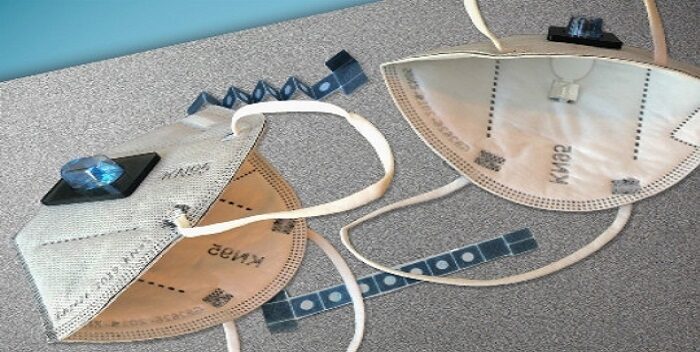

Un equipo de investigadores ha diseñado una mascarilla capaz de detectar, transcurridos unos 10 minutos, si una persona está conversando con otra que está infectada por alguno de los virus más comunes, entre ellos el coronavirus responsable de la covid.

La nueva máscara, que han diseñado en la Universidad Tongji de Shanghai, puede además avisar a los usuarios a través de sus dispositivos móviles de la presencia de esos patógenos en el aire que les rodea.

Los investigadores, que han publicado hoy las conclusiones de su trabajo en la revista Matter, pusieron el foco, tras las evidencias de que las mascarillas pueden reducir el riesgo de propagar y de contraer la enfermedad, en diseñar una que fuera capaz de detectar la presencia del virus en el aire y de alertar al usuario.

El científico Yin Fang, de la citada Universidad, ha subrayado en la publicación que la máscara «funciona muy bien en espacios con poca ventilación, como ascensores o habitaciones cerradas, donde el riesgo de infectarse es alto”, y ha subrayado que en el futuro, si surge un nuevo virus respiratorio, pueden actualizar fácilmente el diseño del sensor para detectar los nuevos patógenos.